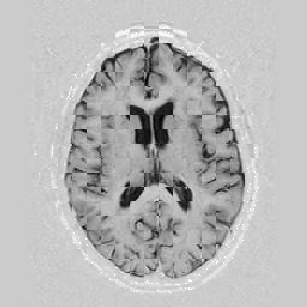

Another larger group of experiments enabled me to study the effects of multi-scale NRR. The results are shown in the form of chequerboard images in Figure [*]. In terms of resolution levels, higher numbers mean that the images are coarser.

Judging by some later stages when resolution is increased, the conclusion reached is that the added computational effort, which is enormous, makes this increase unneeded. The increase in resolution does not reveal much new information about the image structure, at least not at the stage when registration is still far from being entirely approached.

Figure: Multi-scale NRR (increasing resolution). From left to right, top then bottom:before NRR; after 5 iterations of NRR at level 2 (higher is coarser); after another 5 iterations of NRR at level 1.